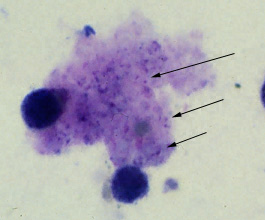

Pneumocystis carinii